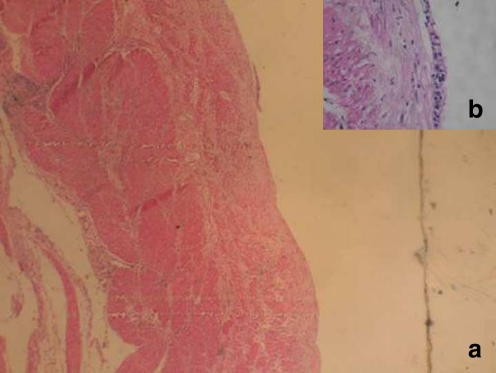

The patient was taken up for surgery. Transhiatal excision of the tumor was attempted. However, the mass which was cystic got ruptured inadvertently discharging thick brownish fluid. The wall of the cyst was then excised from the wall of the lower esophagus. After excision, the defect in the esophageal muscle was closed primarily. No mucosal injury was noted. Histopathological examination of the cyst wall showed evidence of two muscle layers; the epithelium, which was of pseudostratified columnar type, had eroded in most places (Fig. 2). The patient recovered well. Barium evaluation of the patient after 6 months showed a small diverticulum at the site of the excised cyst. However, the patient was asymptomatic with complete relief of her dysphagia.

Fig. 2.

H & E stain of wall of the cyst showing the two muscle coats